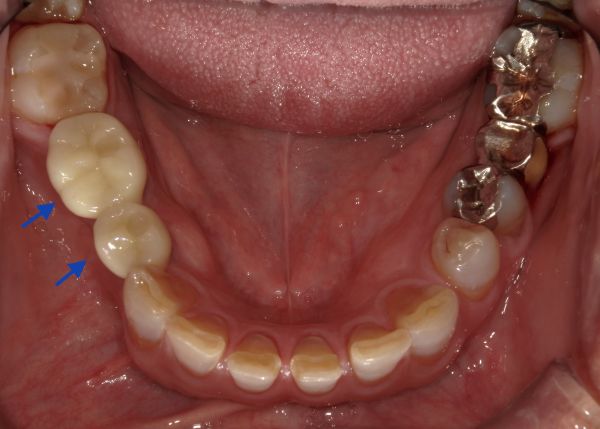

被せ物(ジルコニア)が出来上がってきましたので、微調整を行い、お口の中にセットしました。セット後のお口の中の写真とレントゲン写真がこちらになります。

治療後は違和感なく、ご自身の歯のようにお食事が取れるようになり、インプラント治療を選択されたことにとても満足されております。